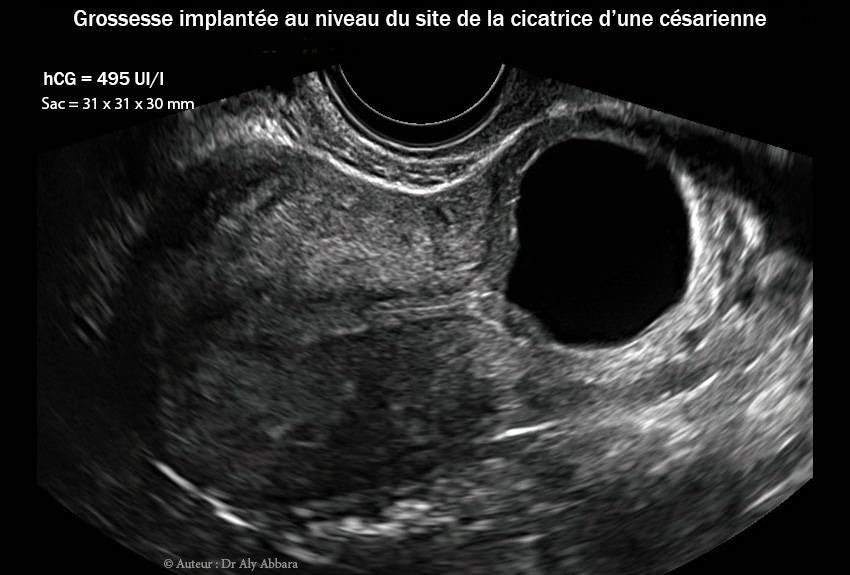

Grossesse-extra-utérine intramurale sur utérus cicatriciel

• Images échographiques par voie endovaginale montrant un sac gestationnel d'une grossesse débutante et partiellement intramurale, implantée dans le site de la cicatrice de l'hystérotomie segmentaire transversale d'une ancienne césarienne.

• L'aspect du sac gestationnel au 8e semaine post traitement médical par méthotrexate : il mesure 31 x 30 x 30 mm de diamètres (= 14,5 cm3) ; le dosage de β-hCG plasmatique était égal à 495 UI/l.

• A ce stade de l'évolution du sac gestationnel, le tissu trophoblastique envahit la paroi antérieure de la zone isthmique de l'utérus et devint en contact avec la paroi vésicale contiguë ; on note aussi la mise en évidence de microvaisseaux naissant au niveau du trophoblaste et pénétrant verticalement dans la paroi vésical juxtaposée (trophoblaste percreta).